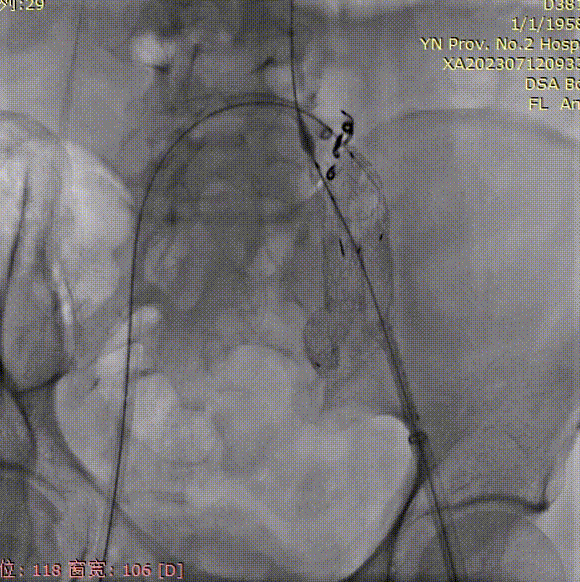

植入第一个右髂内支架;

gore医疗怎么样「漫腹精论」双股动脉入路,纯腔内保双髂——GORE® EXCLUDER® 髂动脉分支型覆膜支架(IBE)治疗双侧髂总动脉_https://www.jmylbn.com_新闻资讯_第25张

植入第二个右髂内支架;

gore医疗怎么样「漫腹精论」双股动脉入路,纯腔内保双髂——GORE® EXCLUDER® 髂动脉分支型覆膜支架(IBE)治疗双侧髂总动脉_https://www.jmylbn.com_新闻资讯_第26张

使用Coda® 球囊依次扩张贴附接腿处;

gore医疗怎么样「漫腹精论」双股动脉入路,纯腔内保双髂——GORE® EXCLUDER® 髂动脉分支型覆膜支架(IBE)治疗双侧髂总动脉_https://www.jmylbn.com_新闻资讯_第27张

释放IBE主体长腿;